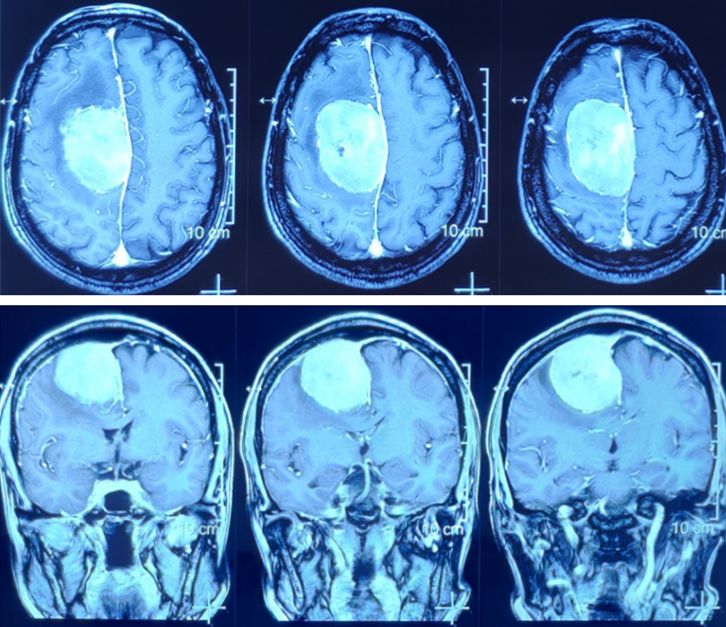

72岁老人,右侧额顶部镰旁巨大脑膜瘤